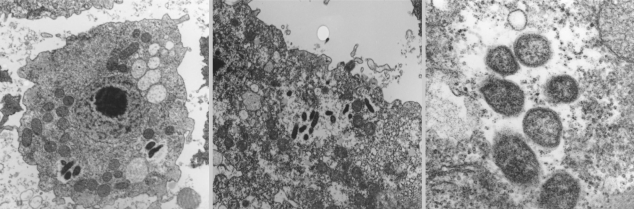

Endosymbionts of Acanthamoeba Isolated from Domestic Tap Water in Korea

The Korean Journal of Parasitology 2009;47(4):337-344.